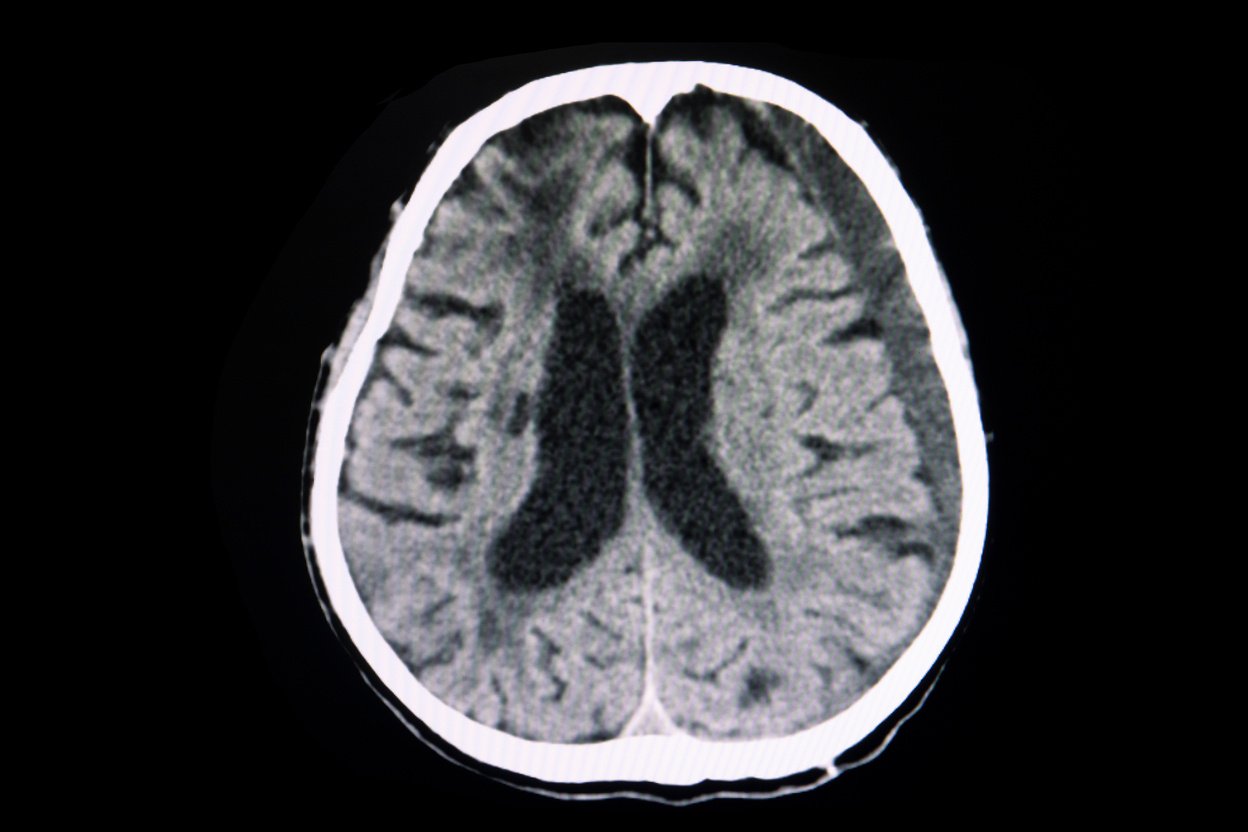

Hidrocefalia

A hidrocefalia é o acumulo de líquido no sistema nervoso. Ela pode acontecer pelo aumento de produção ou pela diminuição da absorção.